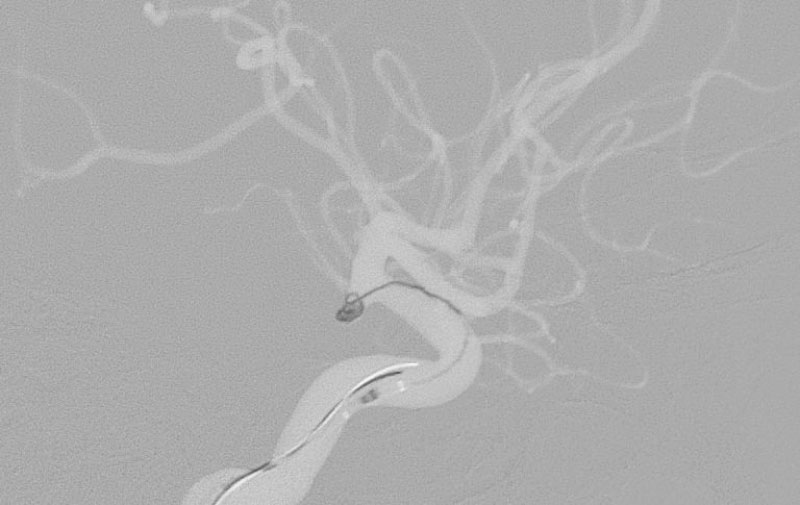

No.1595 手術中

No.1595 手術後